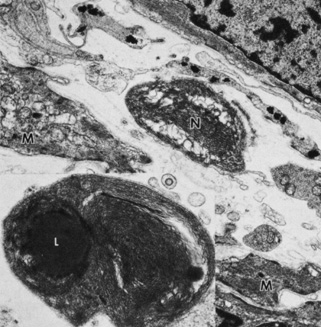

Iris vessels include arterioles, venules, and capillaries. Prior authors have described the light-microscopic morphology of iris blood vessels as “a tube within a tube.”29 It is believed that this angioarchitecture helps to prevent luminal occlusion from folds or kinks created by iris dilation. Iris arterioles are lined with endothelium and surrounded by pericytes (Fig. 16). A longitudinally oriented layer of smooth muscle may be external to the arteriole. External to the muscle is a light collagenous zone, which is in turn surrounded by an outer, dense, collagenous zone. Melanocytes and fibroblasts are found in the adjacent stroma. Iris venules have very thin walls consisting of endothelium surrounded by a thin layer of collagen. Capillaries are formed by a single layer of unfenestrated epithelium. Nerves may be present along larger blood vessels, in the anterior border layer, in the stroma, or among the muscles. Iris nerves are generally unmyelinated, although some may be enclosed by Schwann cells (Fig. 17).

Fig. 17. Myelinated nerve (N) in the iris stroma near the sphincter muscle. Smooth muscle cells are indicated by M (×18,000). Inset shows myelinated nerve with lipid material (L) (×30,000).